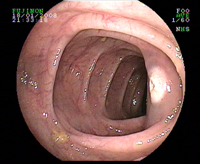

Colon transverse normal